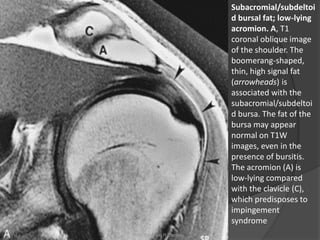

Subacromial/subdeltoi

d bursal fat; low-lying

acromion. A, T1

coronal oblique image

of the shoulder. The

boomerang-shaped,

thin, high signal fat

(arrowheads) is

associated with the

d bursa. The fat of the

bursa may appear

normal on T1W

images, even in the

presence of bursitis.

The acromion (A) is

low-lying compared

with the clavicle (C),

which predisposes to

impingement

syndrome

• 20.

Arco Coracoacromial – AnatomiaNormal  Bolsa subacromial / subdeltóidea:  Um plano de gordura em forma de bumerangue circundando a bolsa subacromial / subdeltóidea é evidente entre a articulação acromioclavicular e o músculo supraespinhal.  A bursa subacromial / subdeltóide normalmente é evidente apenas porque é delineada por gordura.  Ela não deve conter líquido, ou apenas uma quantidade muito pequena. Dr. Emanuel R. Dantas

• 21.

Subacromial/subdeltoi d bursal fat;low-lying acromion. A, T1 coronal oblique image of the shoulder. The boomerang-shaped, thin, high signal fat (arrowheads) is associated with the subacromial/subdeltoi d bursa. The fat of the bursa may appear normal on T1W images, even in the presence of bursitis. The acromion (A) is low-lying compared with the clavicle (C), which predisposes to impingement syndrome Dr. Emanuel R. Dantas